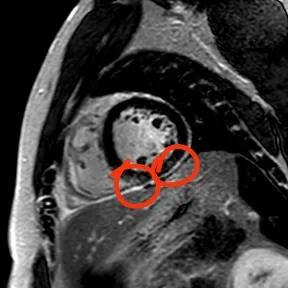

“快!做磁共振觀察心肌有無受損及程度?!庇跋裨\療中心陳寶瑩副主任為小燁進(jìn)行心臟磁共振平掃及增強(qiáng)掃描。結(jié)果提示:患者有急性心肌損傷,考慮心肌梗死。結(jié)果驗(yàn)證了小燁的心肌大片區(qū)失活。

方向比努力更重要,對(duì)于醫(yī)生而言更是如此,準(zhǔn)確把握病因方向,才能有效治療。心臟磁共振,成為非侵入性診斷心肌疾病的金標(biāo)準(zhǔn),能準(zhǔn)確地鑒別心肌炎、應(yīng)激性心肌病、心肌病淀粉樣變性、擴(kuò)張性心肌病及心肌梗死等,并能對(duì)心肌梗死后心肌纖維化進(jìn)行定量評(píng)估。